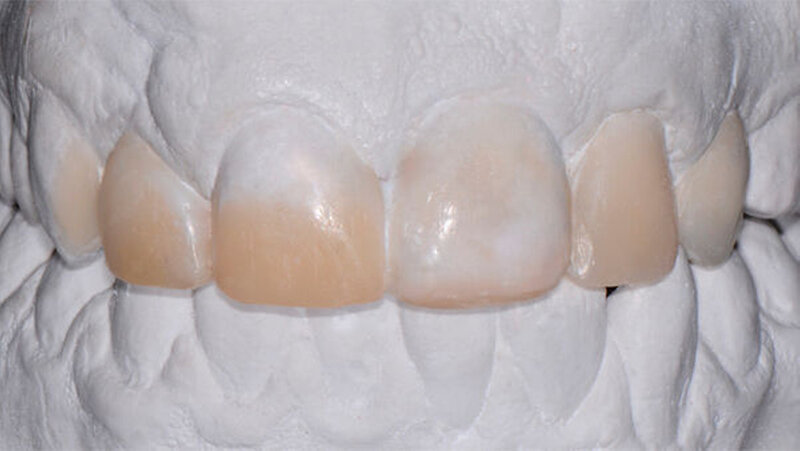

Bei diesem komplexen Fall musste mit Hilfe eines Wax-up ein Silikonschlüssel angefertigt werden, um die Formen aller Frontzähne sicher modifizieren zu können.Ceram.X Duo ermöglichte eine optimale Schichttechnik mit verschiedenen Opazitäten.

Das Alter des Patienten (17 Jahre) spielte hier eine wichtige Rolle. Der Behandlungsplan sollte möglichst keine indirekten Restaurationen beinhalten und eine eventuelle Weiterentwicklung der dentalen Situation berücksichtigen. Deshalb wurde eine minimal-invasive Lösung gewählt, und die beschriebene Schichttechnik erschien angebracht.